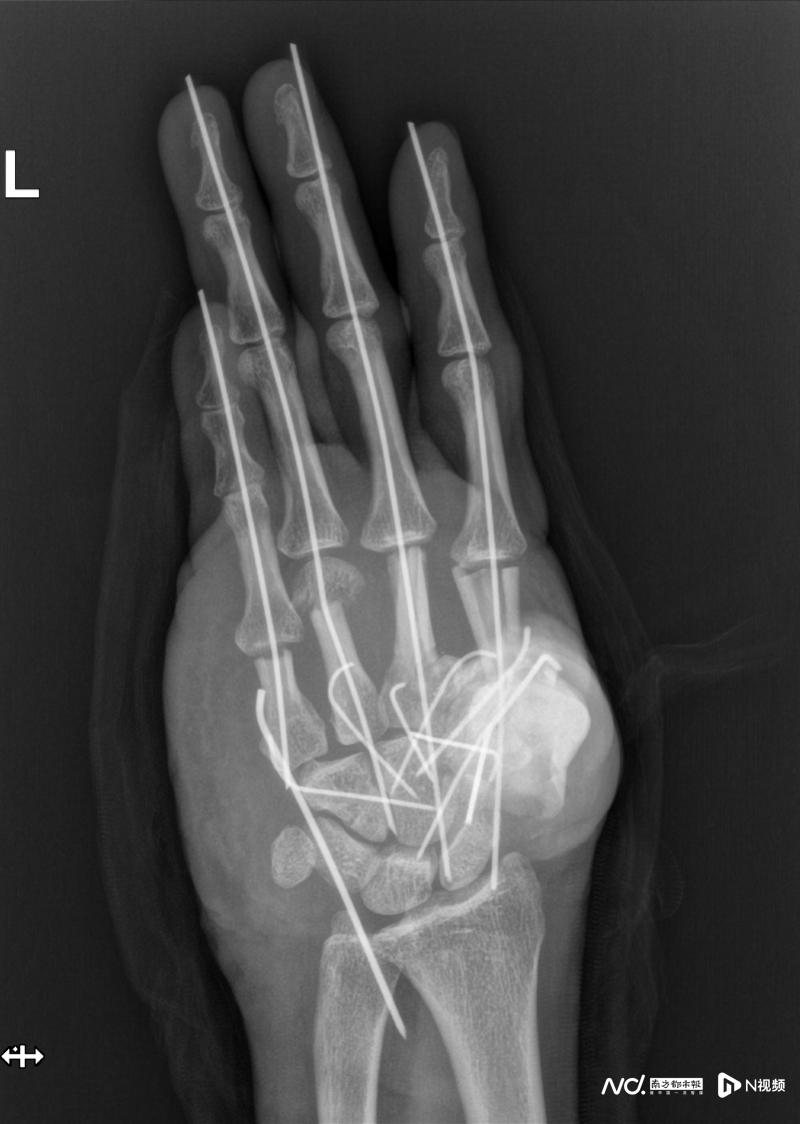

時間就是生機!王小立團隊迅速啟動急診綠色通道,1小時內(nèi)完成術(shù)前準(zhǔn)備并制定詳細方案。無影燈下,手術(shù)分秒必爭:團隊首先徹底清創(chuàng),清除拇指毀損部分及粉碎骨塊,隨后對掌骨、腕掌關(guān)節(jié)進行精準(zhǔn)復(fù)位,用克氏針固定骨折端。

真正的挑戰(zhàn)在于重建左手血運。由于手掌、手背的主干血管嚴重損毀,醫(yī)生決定從患者右足內(nèi)側(cè)截取大隱靜脈,將其裁剪成多段“血管橋”,像繡花般精細吻合至左手掌背側(cè)。“每條血管直徑不足2毫米,需在顯微鏡下一針一線縫合,稍有不慎就會導(dǎo)致失敗。”何天頌解釋,團隊最終完成11條血管(共22個吻合口)的橋接,成功恢復(fù)各指體血供。

手術(shù)團隊連續(xù)奮戰(zhàn)11小時,成功挽救了傷者的手掌。